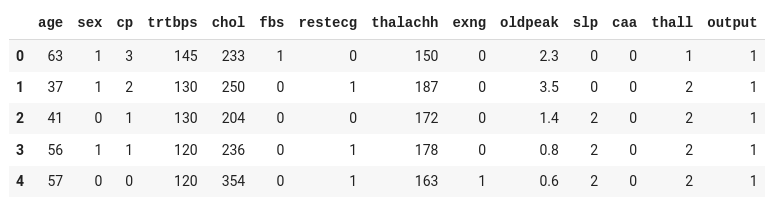

The dataset contains thirteen input columns (age, sex, cp, and so on) and one output column ( output ), which will contain the data as either 0 or 1 .

Considering the input readings, 0 in the output represents the person will not get heart attack, while the 1 represents the person will be affected by heart attack.

Let's split our input and output from the above dataset to train our model:

Since our objective is to predict the likelihood of a heart attack (0 or 1), represented by the target column, we split that into a separate dataset.